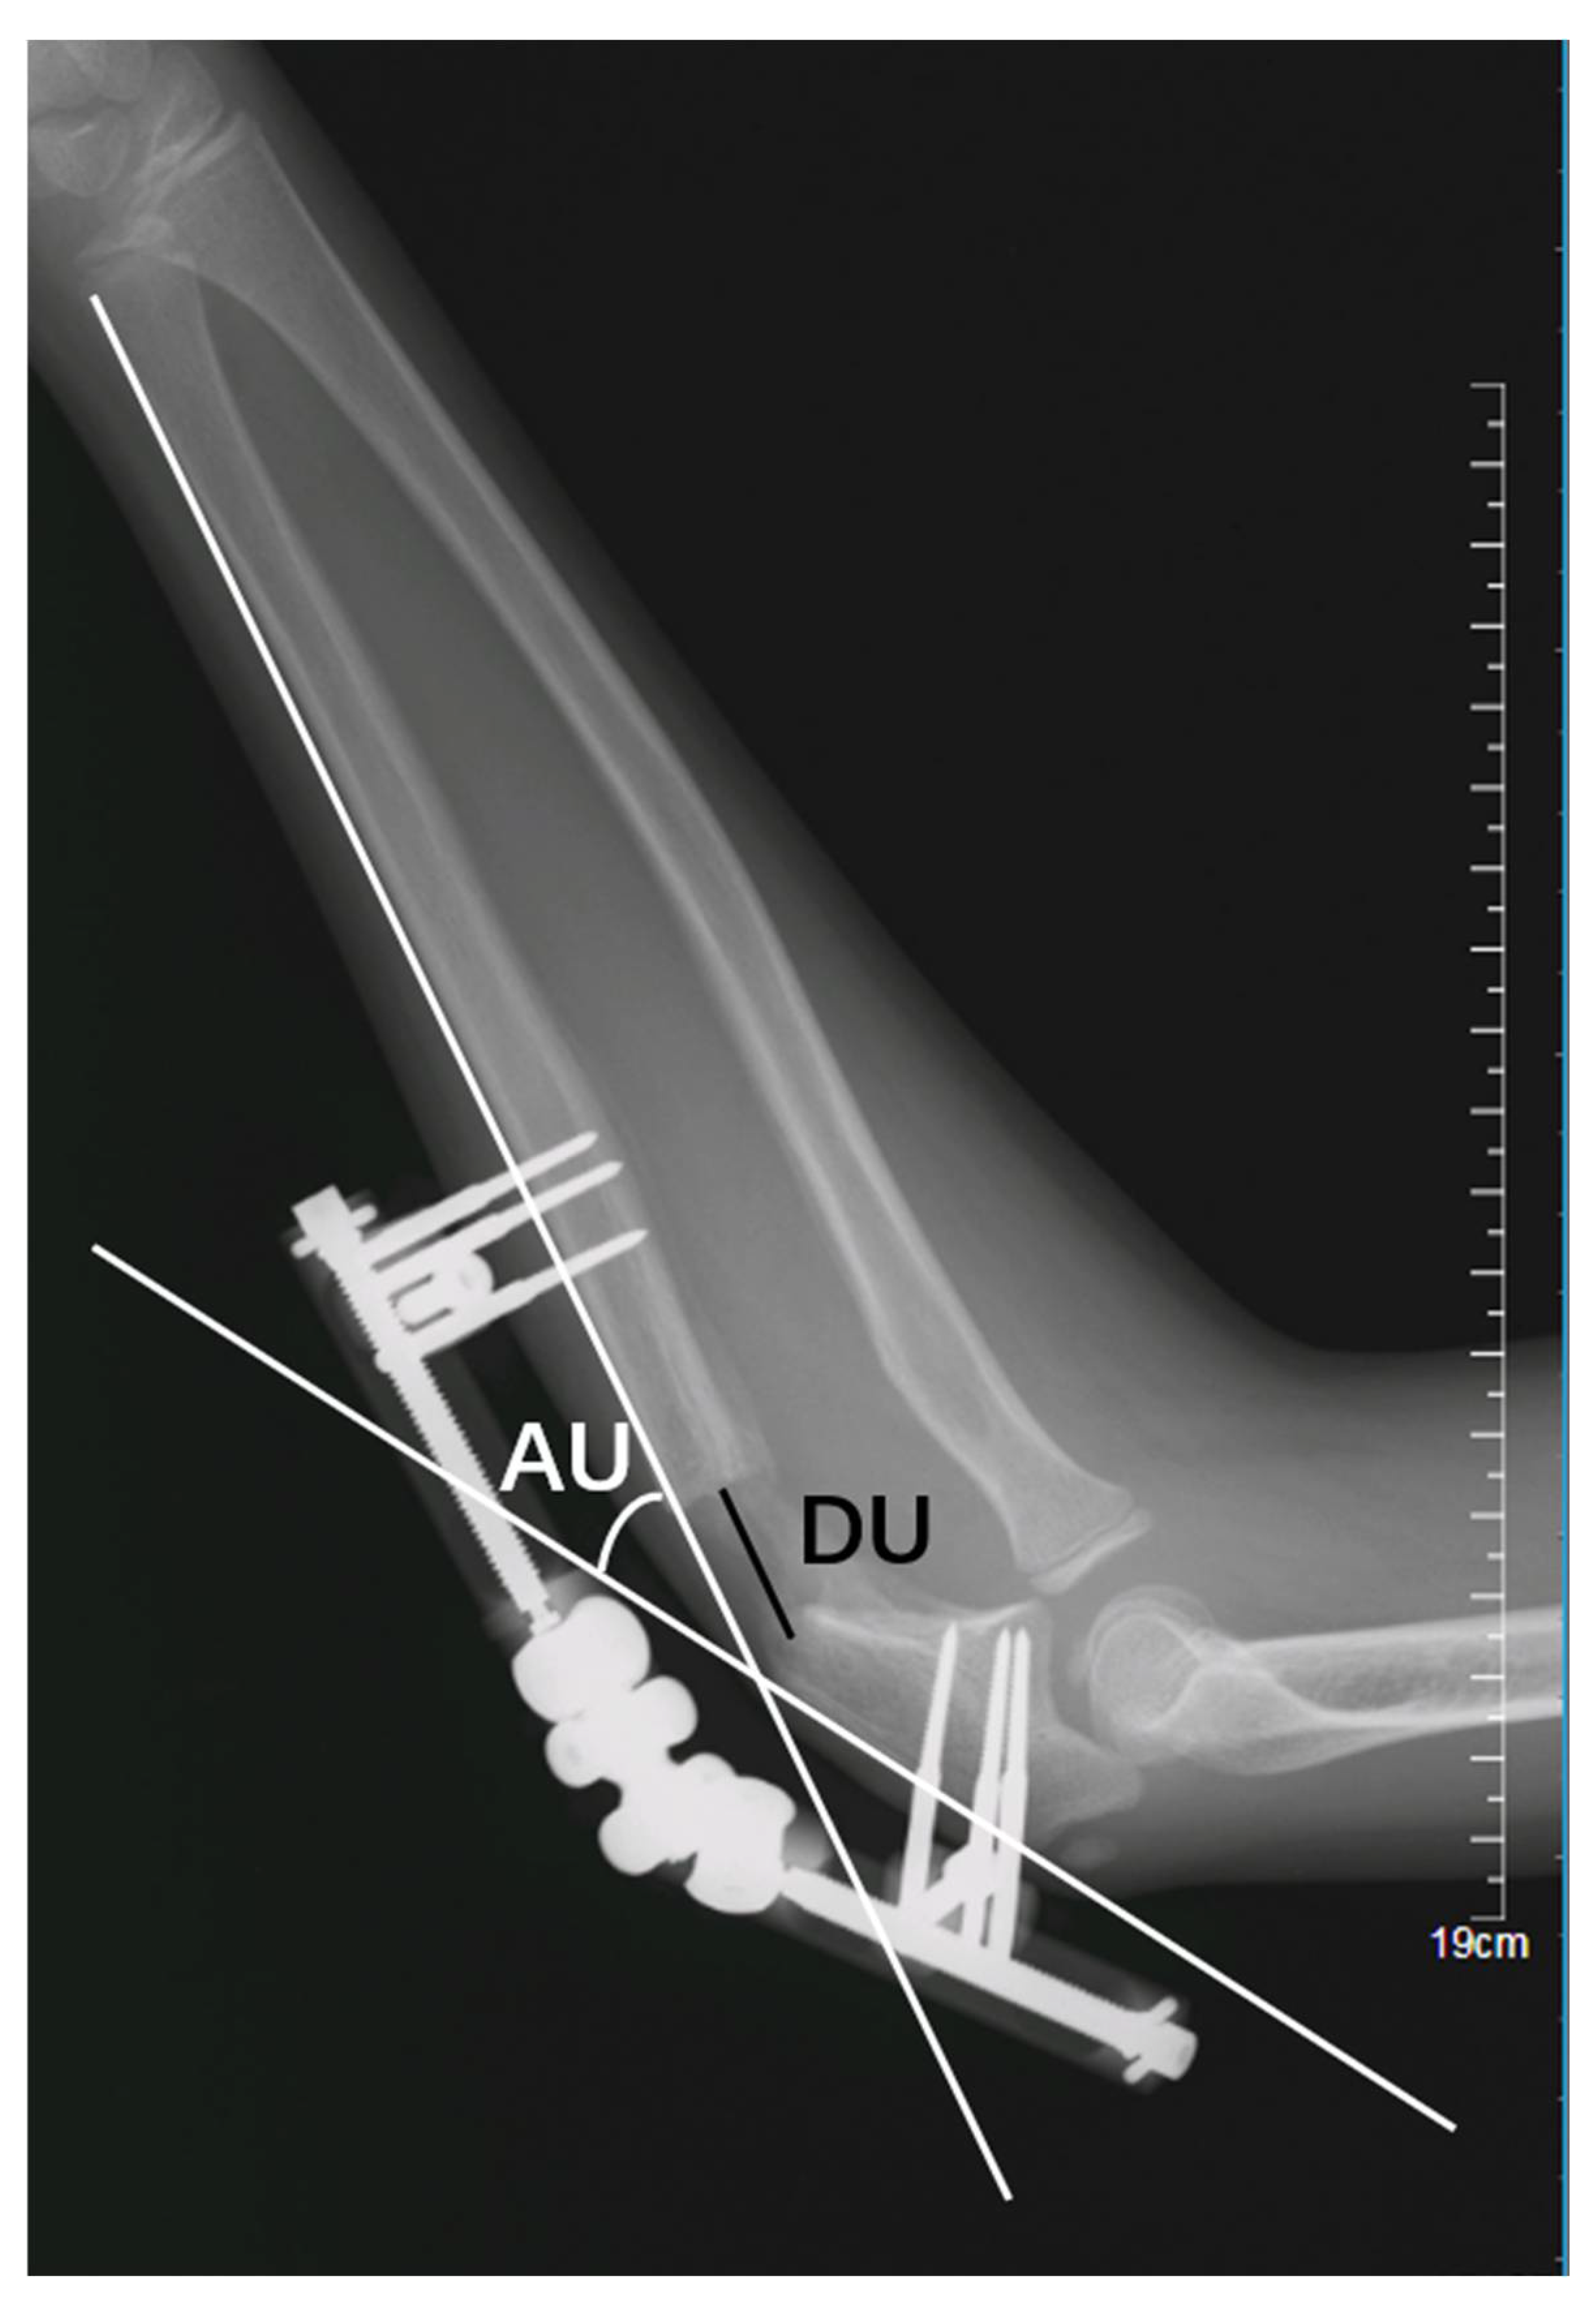

- (1)

- Lengthening distance of the ulna (DU): the distance, in millimetres (mm), between the proximal and distal fragments of the fractured ulna (Figure 3); and

- (2)

- Angulation of the ulna (AU): the angle, in degrees, between the line passing at the level of posterior cortex of the proximal and the distal fragment of the fractured ulna (Figure 3);